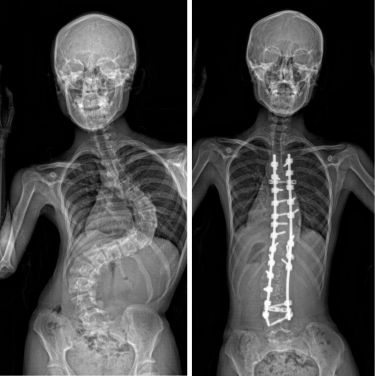

AIS案例

在這項研究中,AIS患者林小姐和羅小姐是重要案例。兩人均於青少年時期患有嚴重的脊柱側彎,亦因此曾於大口環根德公爵夫人兒童醫院接受過脊柱畸形矯正手術。隨後,研究團隊陸續發現她們家族中多名成員均患有脊柱側彎,分別為林小姐及羅小姐家族成員中的61%及50%,團隊亦發現這些成員帶有遺傳性SLC6A9基因變異,部分家族成員亦需要接受矯正手術。